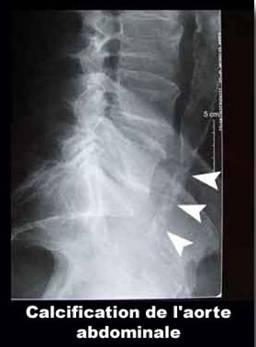

Anevrism de aorta abdominala sub renale intinsa la arterele iliace

primitive.

Arteriografie.

Voluminos anevrism de aorta abdominala sub renale cu important tromb mural

si fine calcificari periferice anterioare. Scanner de aorta abdominala.

Cupe axiale cu injectare i.v. de produs de contrast iodat.

Lumenul arterial rezidual este excentric.